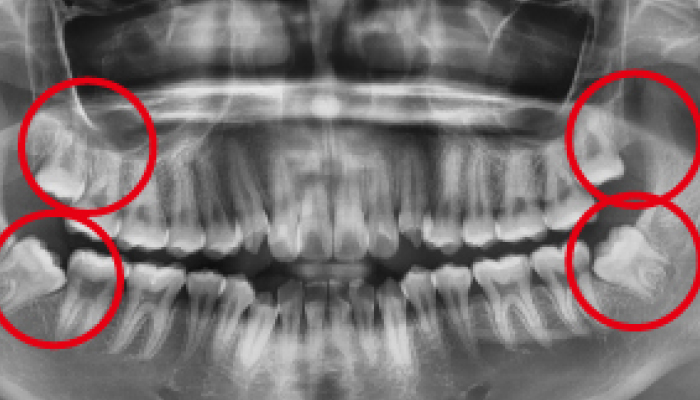

사랑니 발치 전후 사례

• 치료 전

치료 후